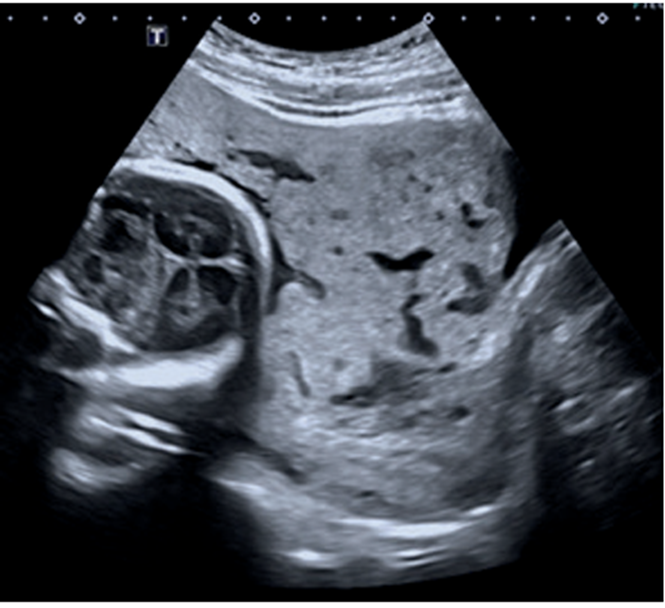

La paciente es valorada inicialmente por la Unidad de Diagnóstico Prenatal del Centro Hospitalario Pereira Rossell, donde cursando un embarazo de 31 semanas de edad gestacional, se realiza la sospecha diagnóstica de acretismo placentario. Se destaca de las imágenes elementos característicos de acretismo, como son, placenta previa oclusiva total con un aumento de su vascularización, pérdida de área hipoecoica retroplacentaria, abundantes lagunas placentarias y pérdida de diferenciación con miometrio en área del segmento (figura 1,figura 2,figura 3).